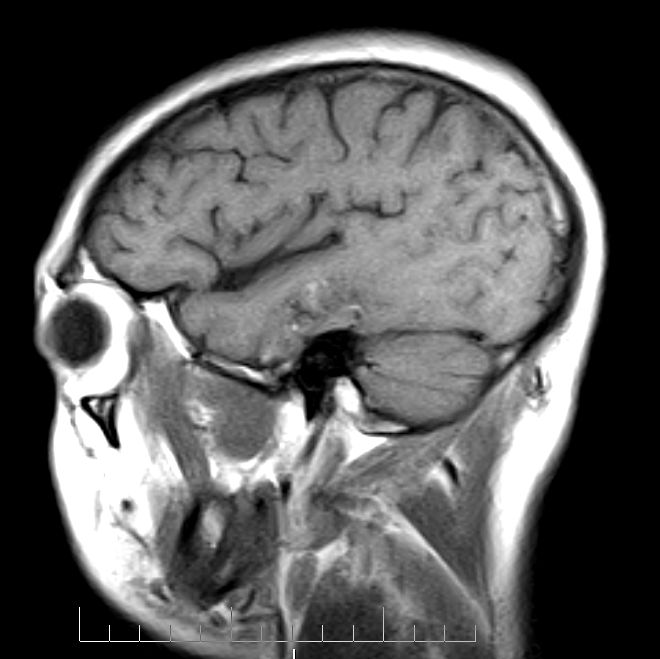

标题: MRI2379:30岁,男,癫痫10年,请各位看一下;CT示:左颞叶钙 [打印本页]

标题: MRI2379:30岁,男,癫痫10年,请各位看一下;CT示:左颞叶钙

左颞叶区见不规则点状混杂信号影

考虑血管畸形

支持2楼 左颞叶区见不规则点状混杂信号影,考虑动静脉畸形。

考虑左侧颞叶脑血管畸形(avm)。

考虑左侧颞叶脑血管畸形(avm)。----t1低等高混杂信号,t2等高信号周边较多流空血管影[冠状位明显],mra左侧大脑中动脉受压,远侧聚集.